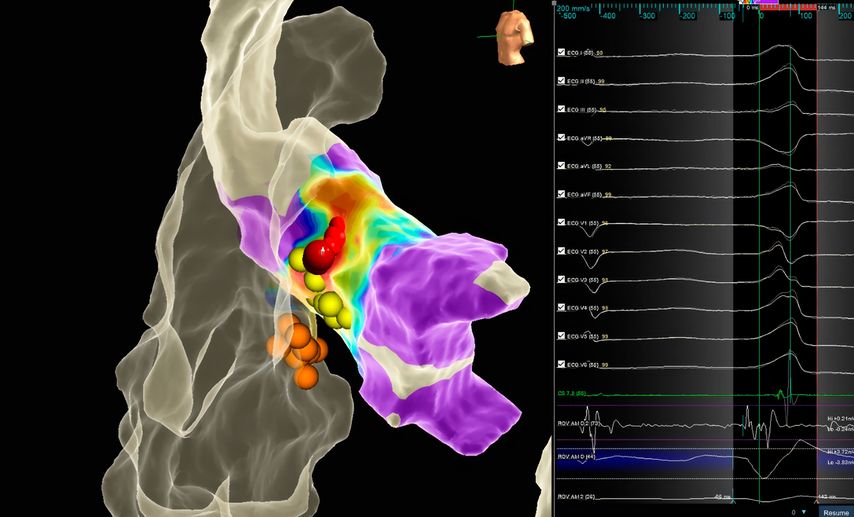

Die hochauflösenden 3D-Mapping-Systeme sind insbesondere dann von kritischer Bedeutung, wenn sehr sensible Strukturen im Rahmen der Ablation geschont werden sollen. In Abbildung 3 ist die erfolgreiche Ablation einer Ausflusstraktextrasystolie im Bereich der Aortenwurzel in unmittelbarer Nähe zum intrinsischen Reizleitungssystem (HIS-Signale) dargestellt.

Abb. 3: Elektroanatomische Rekonstruktion mit Aktivierungsmapping des linksventrikulären Ausflusstrakts/Aortenwurzel mit Ursprung der Extrasystolie in unmittelbarer Nähe zum intrinsischen Reizleitungssystem (HIS-Signal, gelbe Punkte). Erfolgreiche Ablation (rote Punkte) mit vorsichtiger Annäherung an die HIS-Punkte ohne Verlängerung der PQ-Zeit